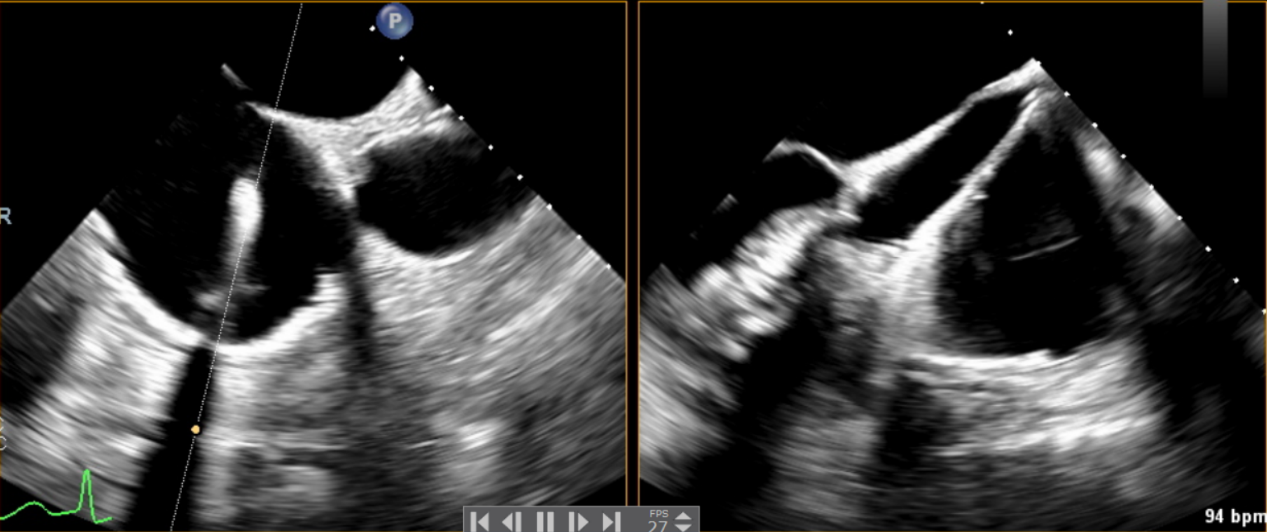

術(shù)中輸送器在超聲引導(dǎo)下調(diào)整位置